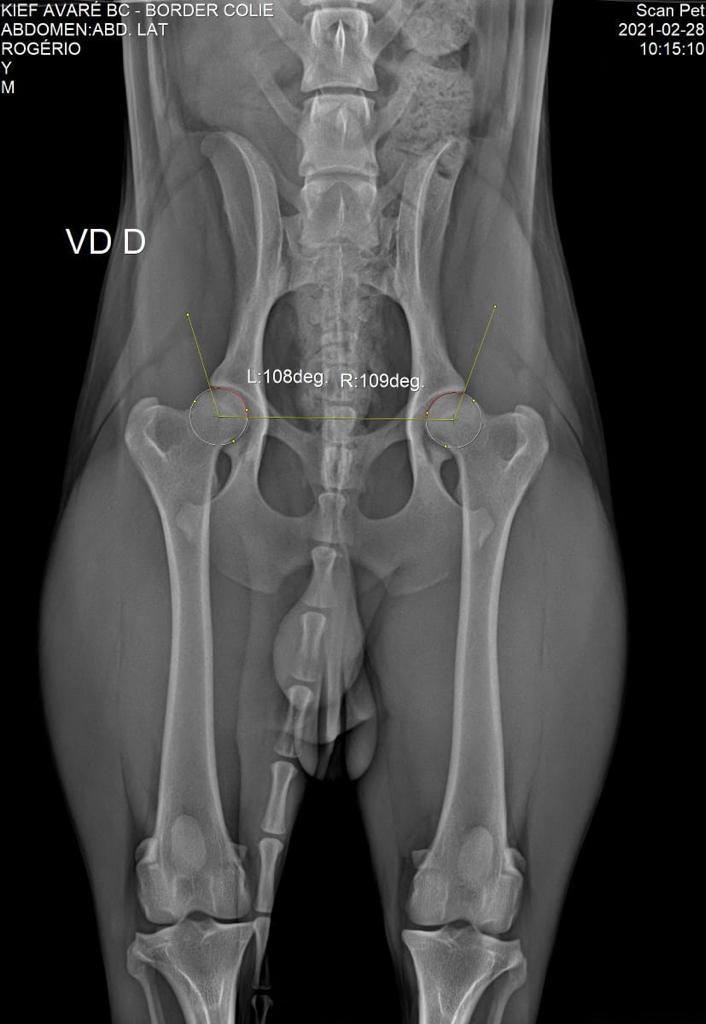

DISPLASIA

28/02/2021

ADEQUADO GRAU A

SCANPET

LAUDO

CHAPA